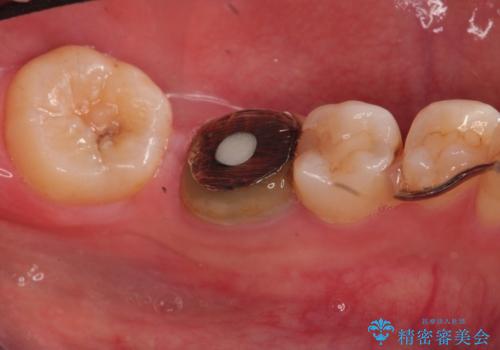

- 下顎の銀歯と、かぶせ物が外れたままになっている歯の治療を主訴に来院されました。

左下の奥歯はかぶせ物が外れて、土台が露出している状態でした。